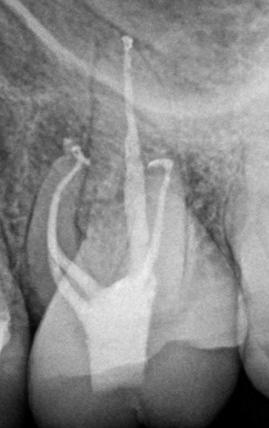

We are proud to announce that we have partnered with Zarc4Endo, a company founded and operated by Endodontists for Endodontists to bring Avalon Biomed by Zarc, with a portfolio of innovative endodontic file families, corresponding gutta percha and paper points, cordless devices, and accessories, to the U.S market. Based out of Madrid Spain, Zarc launched BlueShaper, the world’s first pink & blue dual alloy system in January 2021. Behind the scenes, over the past year our KOLs across the U.S. have been using this first of its kind file system with performance and quality exceeding all of their expectations.